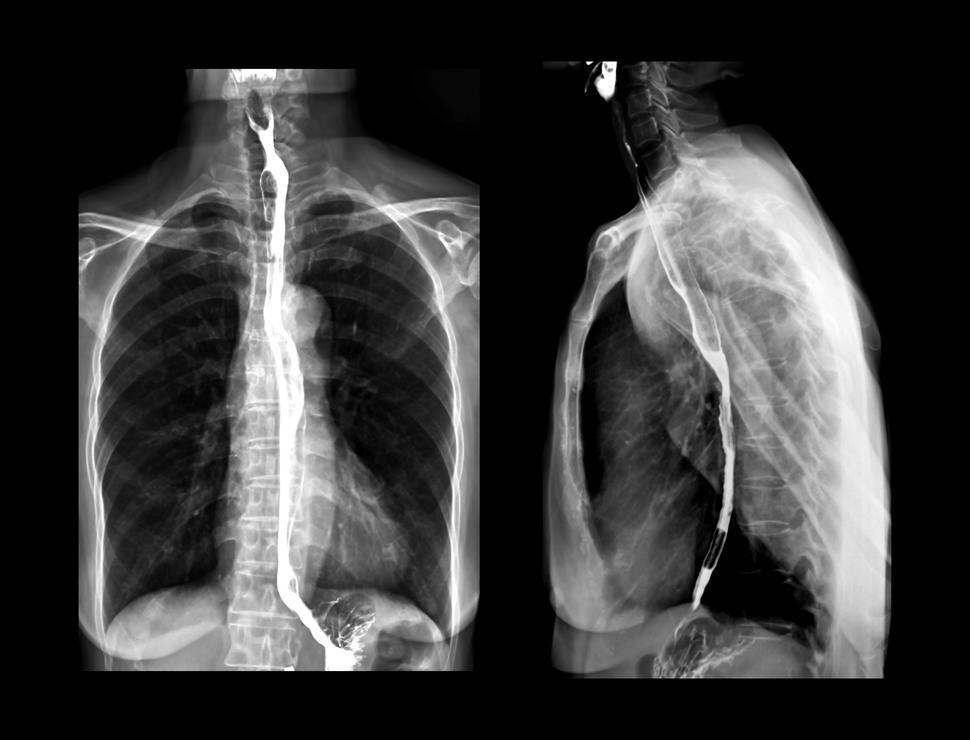

X-ray highlighting the esophagus following a barium swallowing procedure.

An x-ray of the esophagus and upper gastrointestinal tract following a barium swallow test.

Credit: iStock